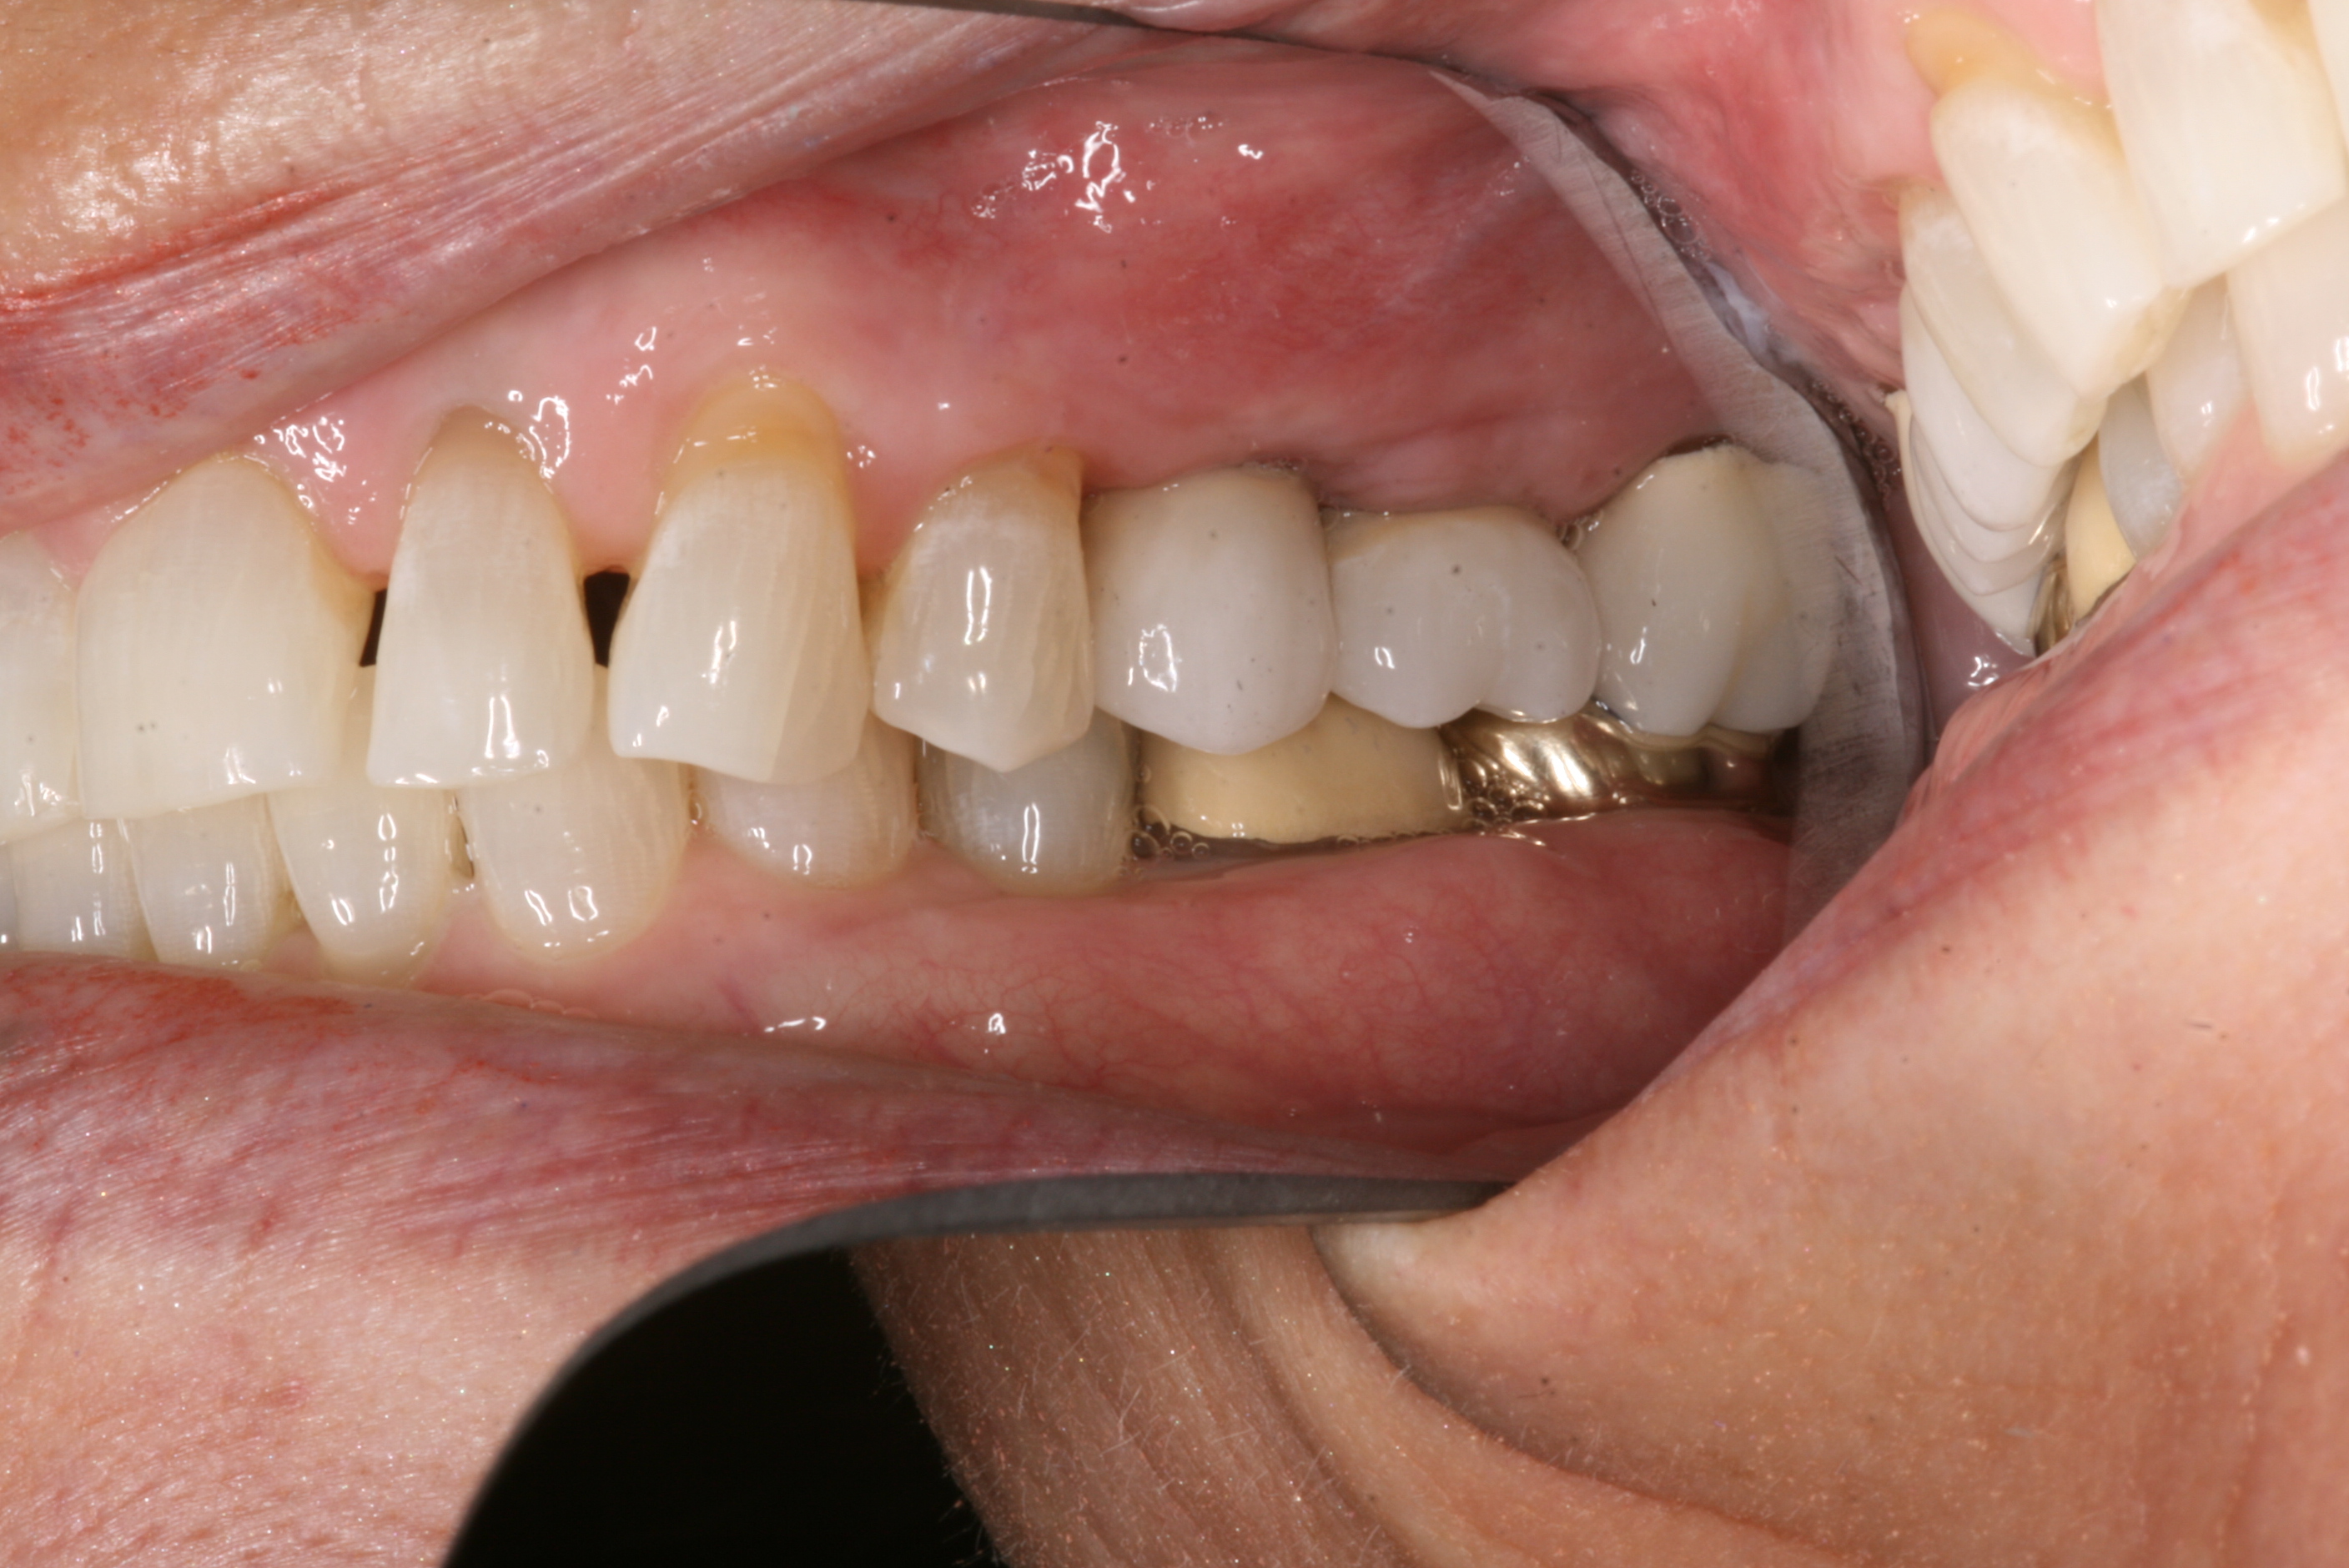

dental implants

Dental implants do more than replace missing teeth—they help you eat, speak, and live with total confidence. At Epperson Payne Dental Group, we combine expert care with the latest technology to deliver results that last.

Getting dental implants is a big decision, and you deserve the absolute best care. Our practice brings everything you need together in one place - from detailed planning to expert surgery to the final artistic touches that make your smile look natural and beautiful.

We combine the latest technology with deep experience in implant dentistry to deliver results you'll love. Whether you need to replace one tooth or restore your full smile, our team focuses on getting every detail right, giving you a comfortable experience and lasting results you can count on.